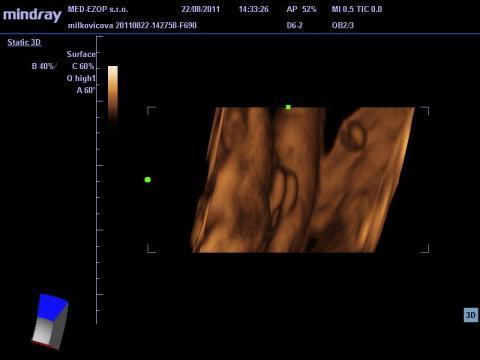

Pro větší náhled klikněte na obrázek

Dobrý deň, poprosím o váš názor, nakoľko som dosť napätá, vzhľadom na tlak okolia, manžela, ktorý túži po vyhranenom pohlaví. Raz mi hovoria na UZ, že to bude chlapec, raz dievča. Naposledy som bola v 34tt. Prikladám foto. Aký je váš názor? Dá sa to jednoznačne potvrdiť? Ďakujem

Pokiaľ ani lekári nie sú si na 100% istí, tak s tým nič nenarobíte a dozviete sa to až po pôrode. Ja si osobne myslím, podľa fotky, ktorú ste poskytla, že to vypadá skôr na dievčatko.

No dle mého názoru to vypadá na chlapečka, 2 varlátka a směrem dolu pinďourek. No nevím ale přeju vám to.

Ale toto je myslím foto odzadu, kolienka hore...prečo je tam tá ryha medzi?

ja som to videla rovnako ako máte Vy na foto, podľa mňa je to dievčatko, aj moja dcéra to tak mala.

Takže dávam na vedomie, že sa narodilo zdravé dievčatko